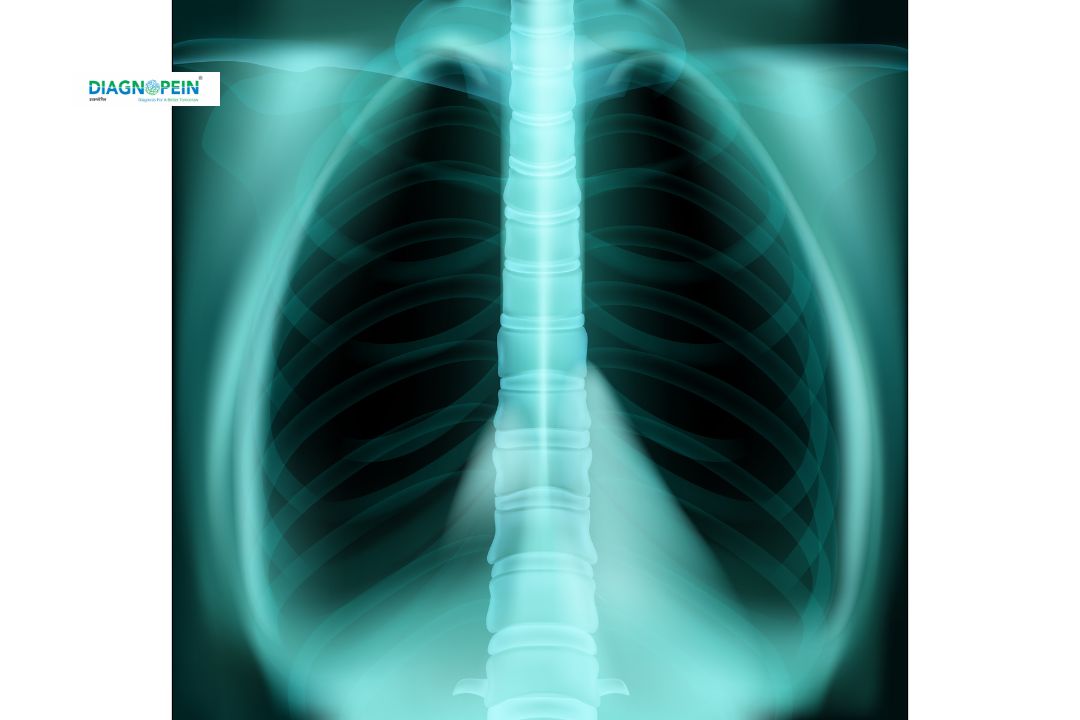

HRCT Thorax (High-Resolution Computed Tomography of the Thorax) is a specialized CT scan that provides highly detailed images of the lungs and chest region. It helps doctors examine the fine structure of lung tissues, bronchi, and blood vessels — crucial in detecting early signs of respiratory or pulmonary diseases.

At Diagnopein, Nashik, we use advanced HRCT technology to give precise cross-sectional images of the chest.